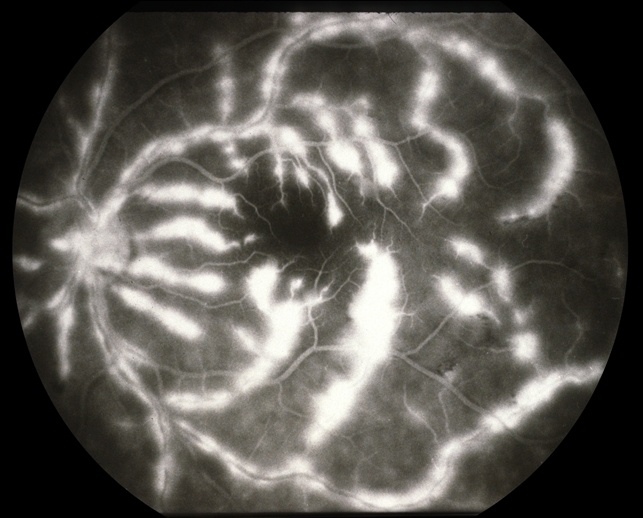

- frosted branch angiitis

- Frosted branch angiitis patient. Left eye: F/A leakage seen as hyperfluorescence along involved vessels. #2